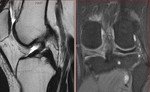

[画像診断]前十字靱帯陳旧性断裂について【後期研修医と学ぶ】 2011-03-25